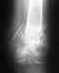

Мне 26 лет, 1,5 года назад 30 сентября 2012, попал в аварию, был оперирован в СКЛИФЕ, дс: оскольчатый перелом средней трети левой бедренной кости со смещением отломков, был выполнен остеосинтез блокируемым штифтом.Был отправлен домой в Иркутск, спустя 8 месяцев консолидации отломков не выявлено, более того, они разошлись.

Был повторно оперирован в Институте ортопедии, удалили штифт и установили аппарат Илизарова, вот спустя 9 месяцев после второй операции, кость срослась ( срощение было медленным, помог препарат Бивалос). Остеосинтез штифтом проводился в закрытом виде, поэтому отломок не был присоединен, во время второй операции он удален, в итоге на задней стенке кости в месте перелома этого кусочка не хватает. Скажите пожалуйста, как будет вести себя место перелома в дальнейшем, зарастет ли место где не хватает кусочка? И еще с передней части кости в месте перелома, образовалась большая костная мозоль, пройдет ли она в дальнейшем и не станет ли она расти дальше?Выложу последние рентгенограммы.